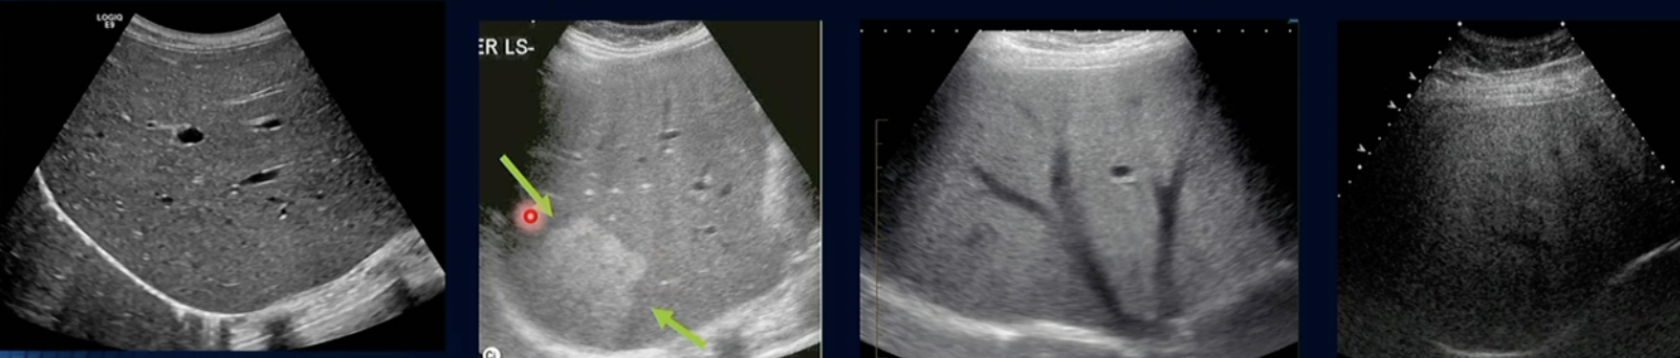

Pathology?

Fat Infiltration

Pathology? Which is Normal and whats the worst

Fatty Infiltration

Hepatitis (Inflammation of Liver due to Echogenic areas)

Difference between Haemangioma + HCC

Haemangioma has no blood vessels/lack of

HCC has blood vessels/blood flow

Haemangioma (due to no colour on it)

HCC due to colour/bloodflow